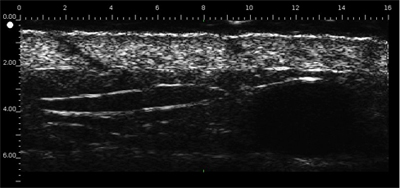

Vieillissement de la peau: Détermination de la SLEB

Le derme est échogène. Les échos proviennent du réseau de fibres collagènes et de fibres élastiques. Par rapport au derme, les lésions (tumeurs, kystes, angiomes…) apparaissent comme des zones hypoéchogènes.